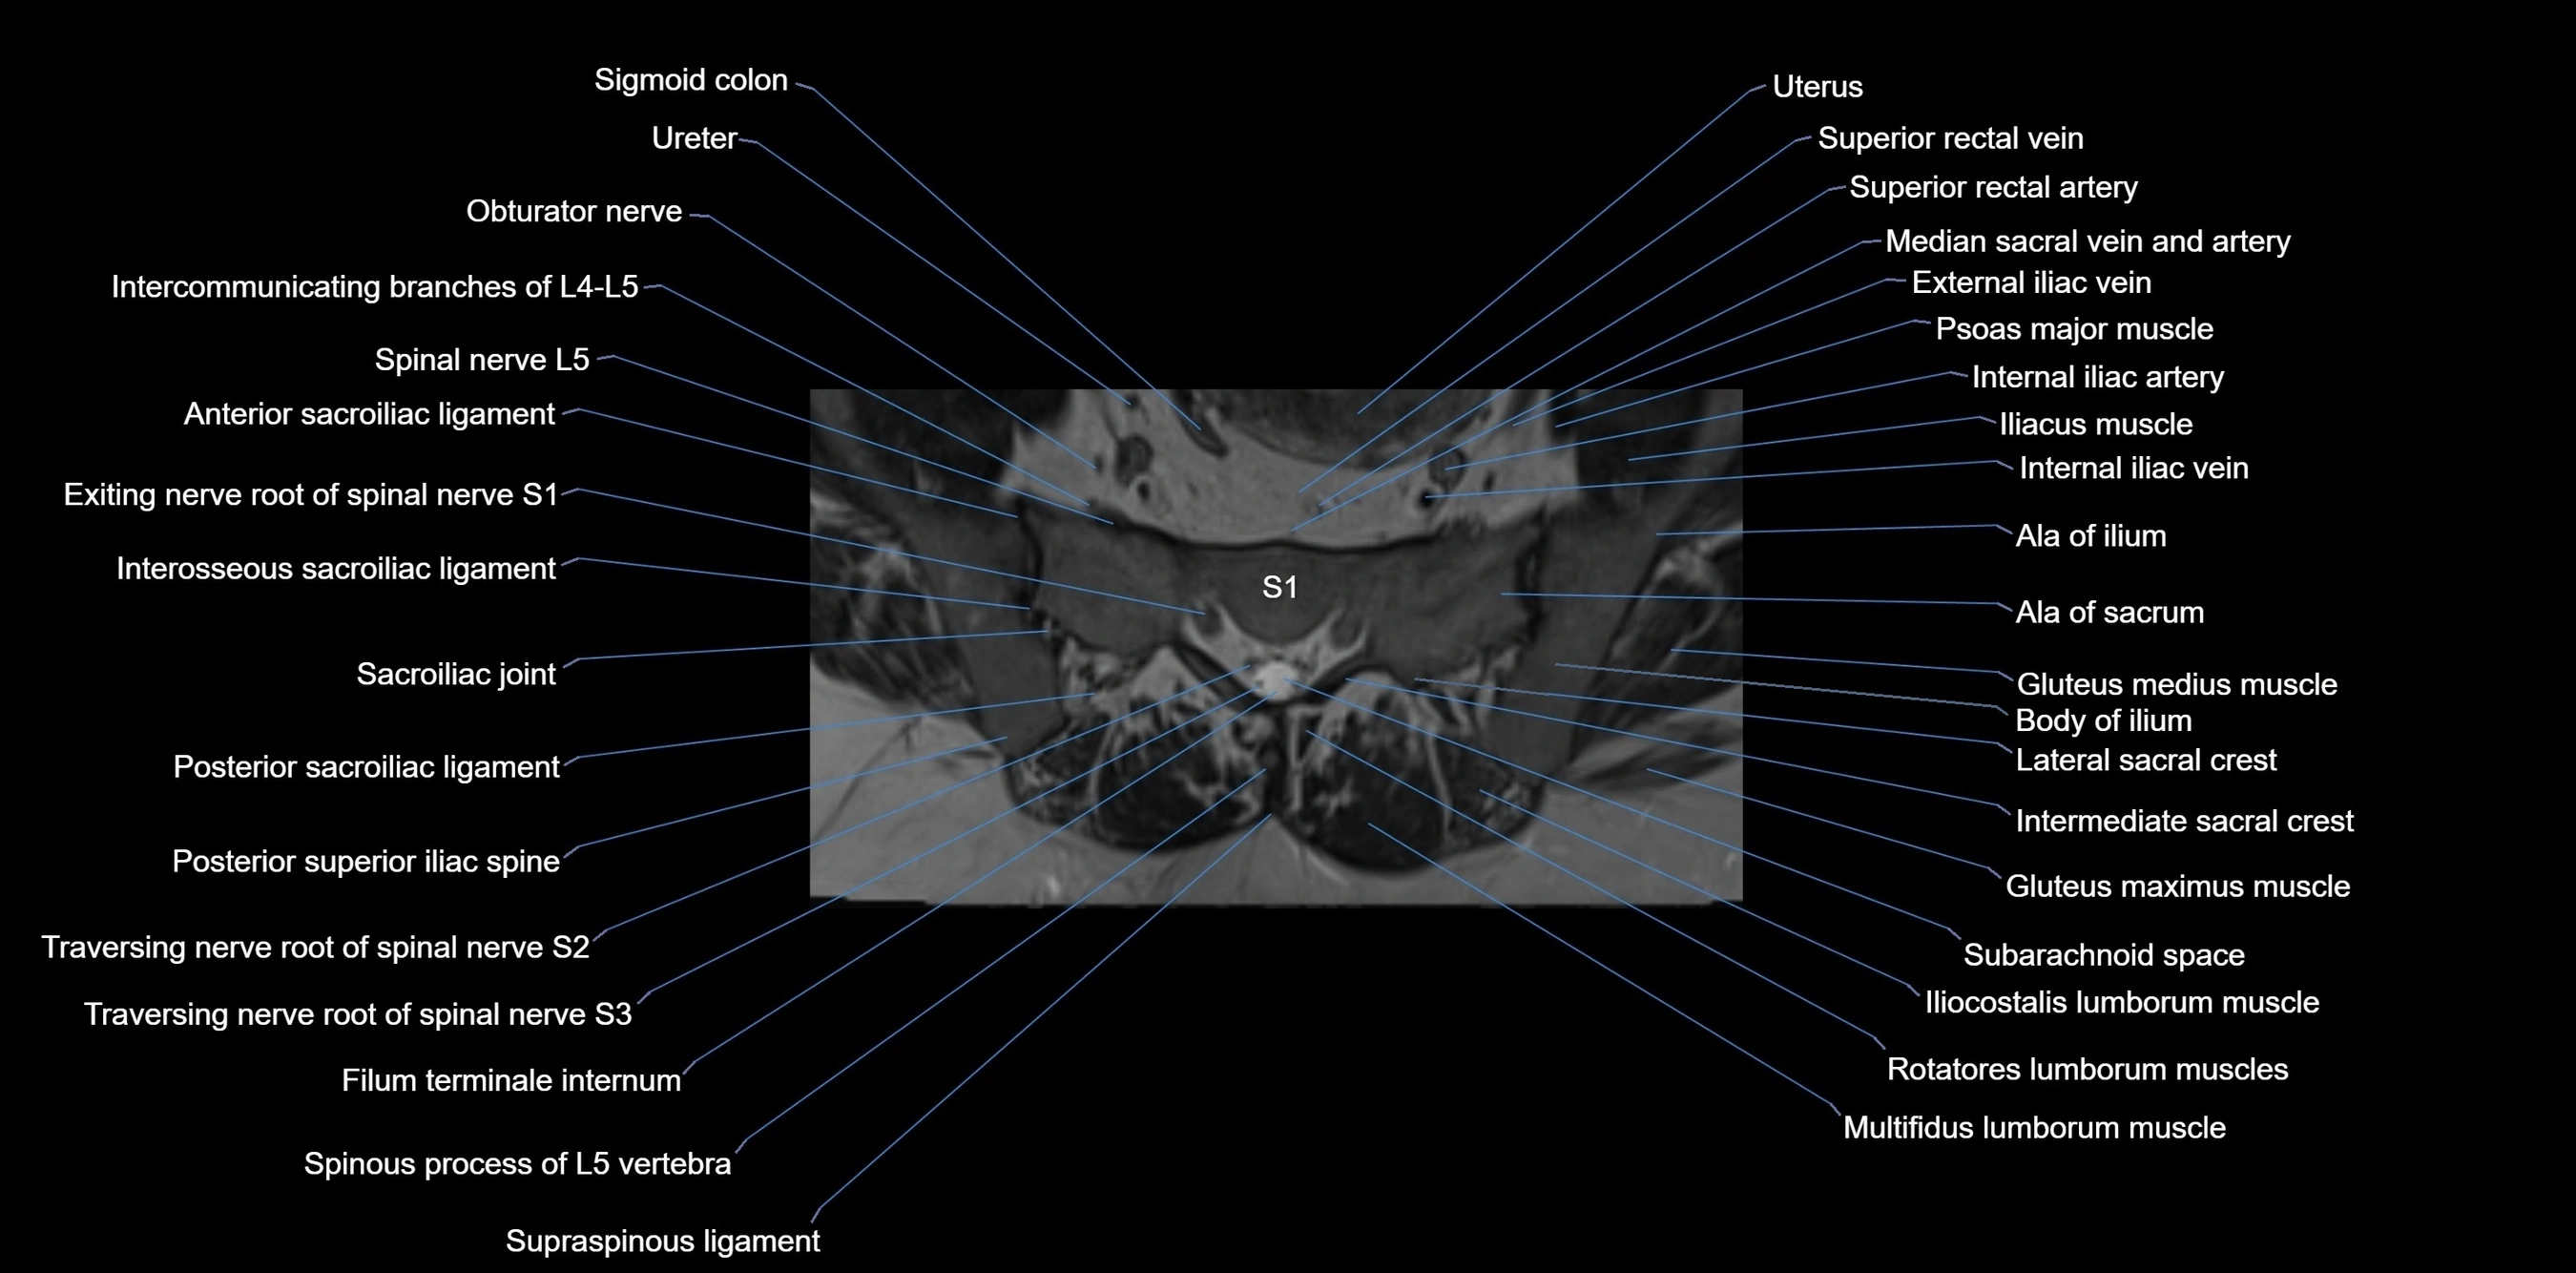

CT VRT image

image